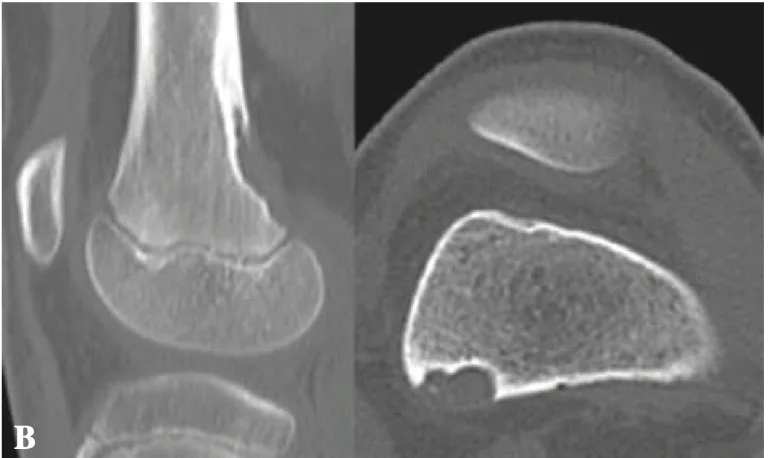

大腿骨の後内側の皮質骨が凹むような病変が認められます.

引用元:Muramatsu K. Distal femoral cortical irregularity in children. Acta Orthop Belg. 2015. 81.

CTの結果, 大腿骨の後内側の皮質骨が凹むような所見を確認し, 診断が確定しました.

遠位大腿骨皮質骨不整は, 小児期から青年期にかけて見られる, 骨腫瘍と誤認されやすい良性・一過性の病変です.

両側性のこともあり, 多くは無症状.

時間の経過とともに自然消失するため, 治療は不要です.